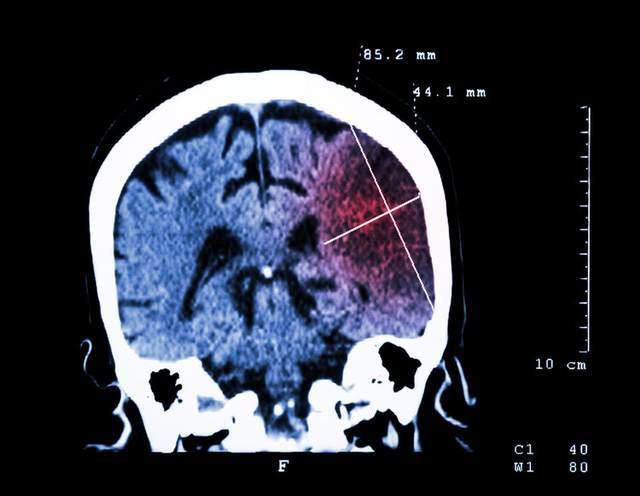

入院后 , 医院给罗奶奶安排了CT检查 , 检查结果显示 , 罗奶奶患有脑干腔隙性脑梗塞以及两侧基底节区腔隙性脑梗塞 。

文章插图

(脑部CT图)

除此之外 , 还伴有主动脉及冠状动脉硬化 , 是极高危的高血压症状 。